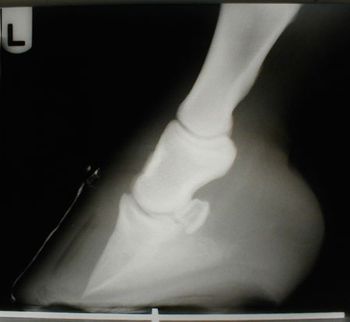

Fort Collins, Colo. - To save a dog's leg, a veterinary orthopedic surgeon tried something radical.